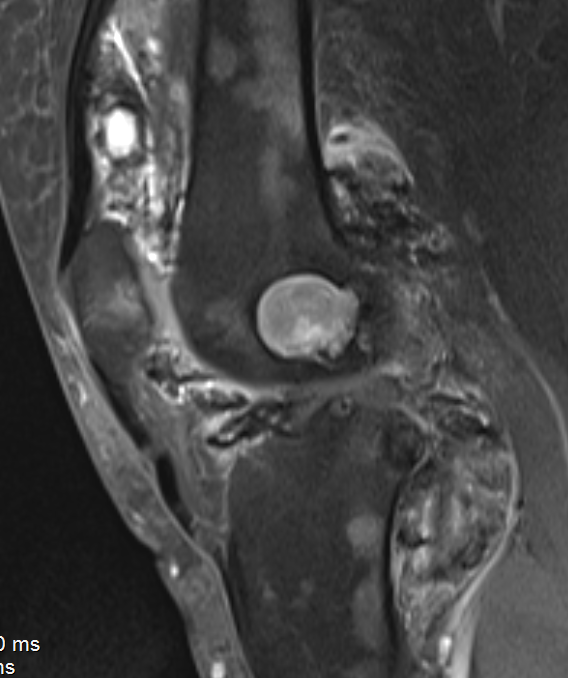

MRI

Synovial thickening

Hemosiderin

- low signal intensity on TI and T2 - "drop out" signals

- blooming on gradient echo

Diffuse

Diffuse PVNS with involvement of suprapatella pouch and posterior compartments, including posterior extra-articular